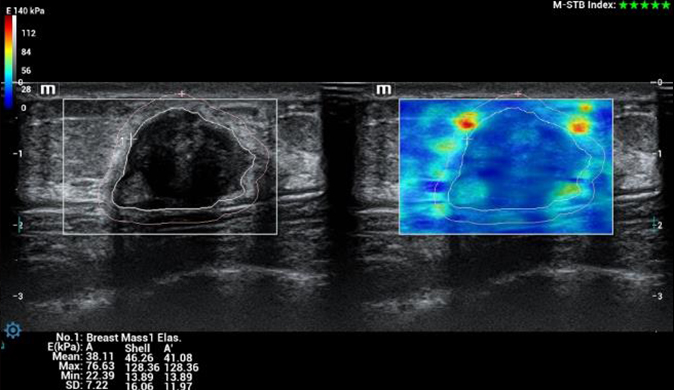

Das Resona I8 weist vielfältige klinische Lösungen auf, die speziell für den jeweiligen Anwendungsbereich entwickelt wurden. Die Technologie baut auf einem tiefgreifenden Verständnis verschiedener klinischer Szenarien auf und bietet eine umfassende Serie fortschrittlicher Diagnoseinstrumente, beispiellose Intelligenz und präzise Analysen zur Verbesserung von Diagnosesicherheit, Qualitätskontrolle und Scaneffizienz.